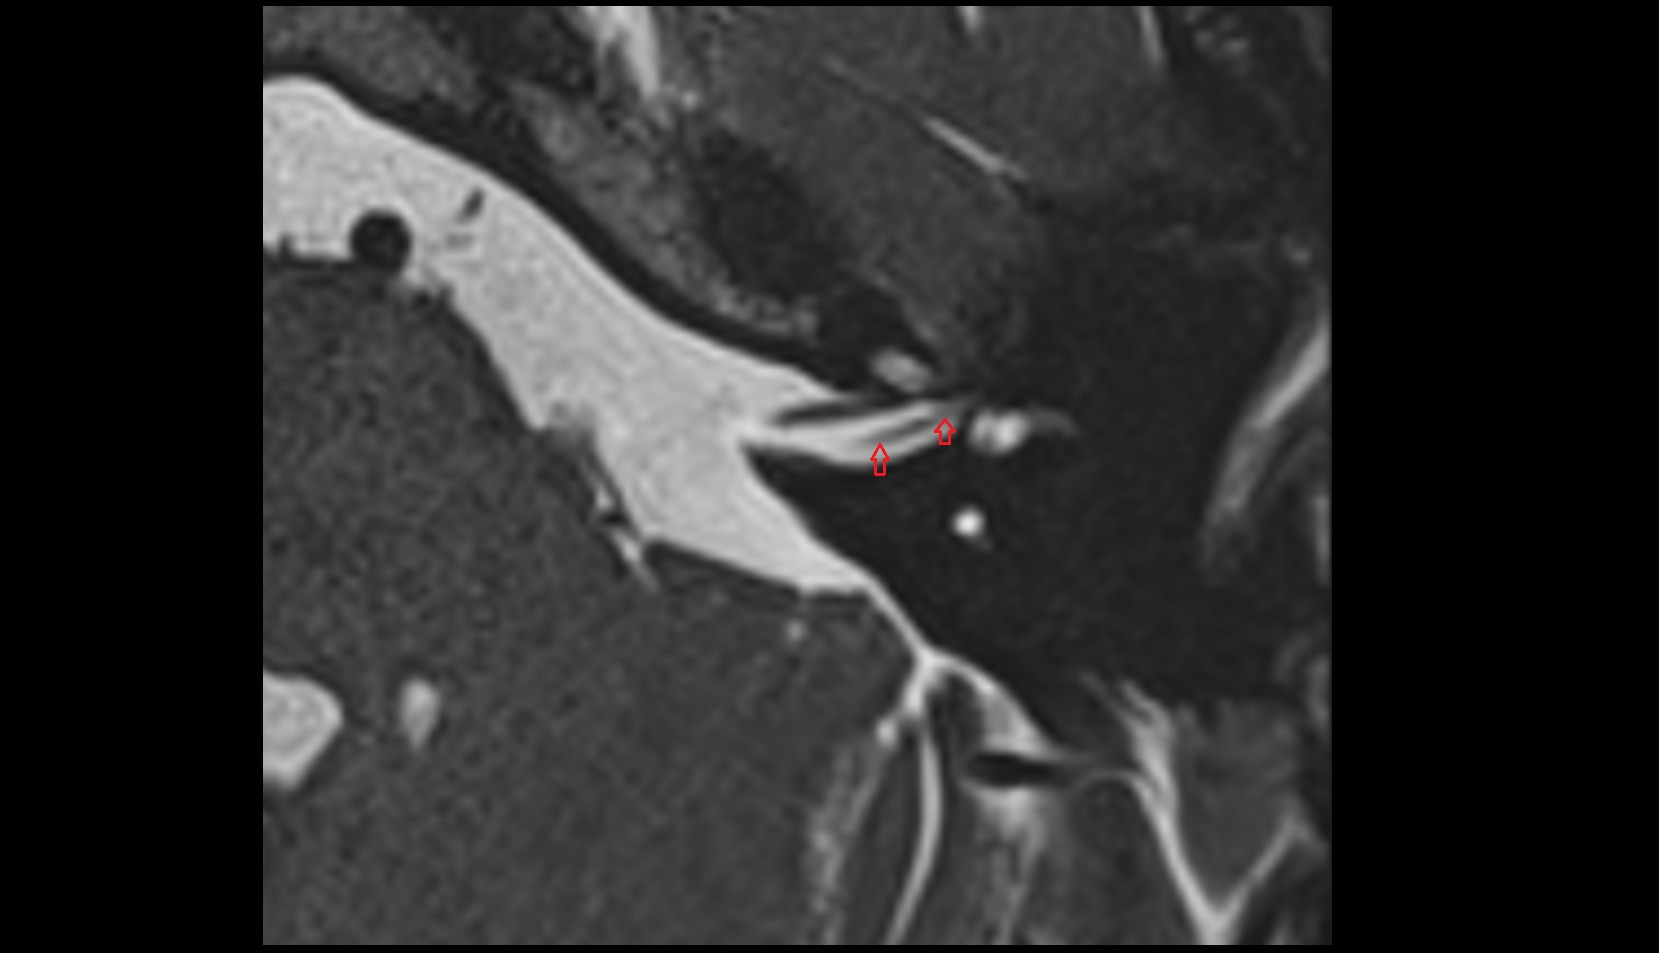

- Temporomandibular joint

- Articular disc of temporomandibular joint

- Articular eminence

- Mandibular condyle

- Mandibular fossa